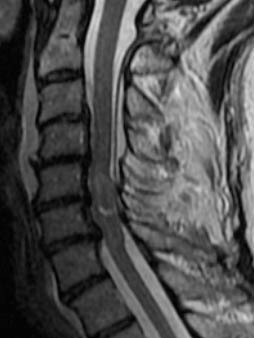

• Tutte le modalità diagnostiche disponibili: Risonanza Magnetica, TAC, Radiologia, Mammografia, Ecografia, MOC, OPT e Cone Beam, Interventistica.

• Apparecchiature di ultimissima generazione, sostituite ogni 4-5 anni.

Le apparecchiature TC ed RM utilizzate assicurano il massimo delle prestazioni (qualità di immagine e velocità di acquisizione) ormai senza più problemi di claustrofobia.